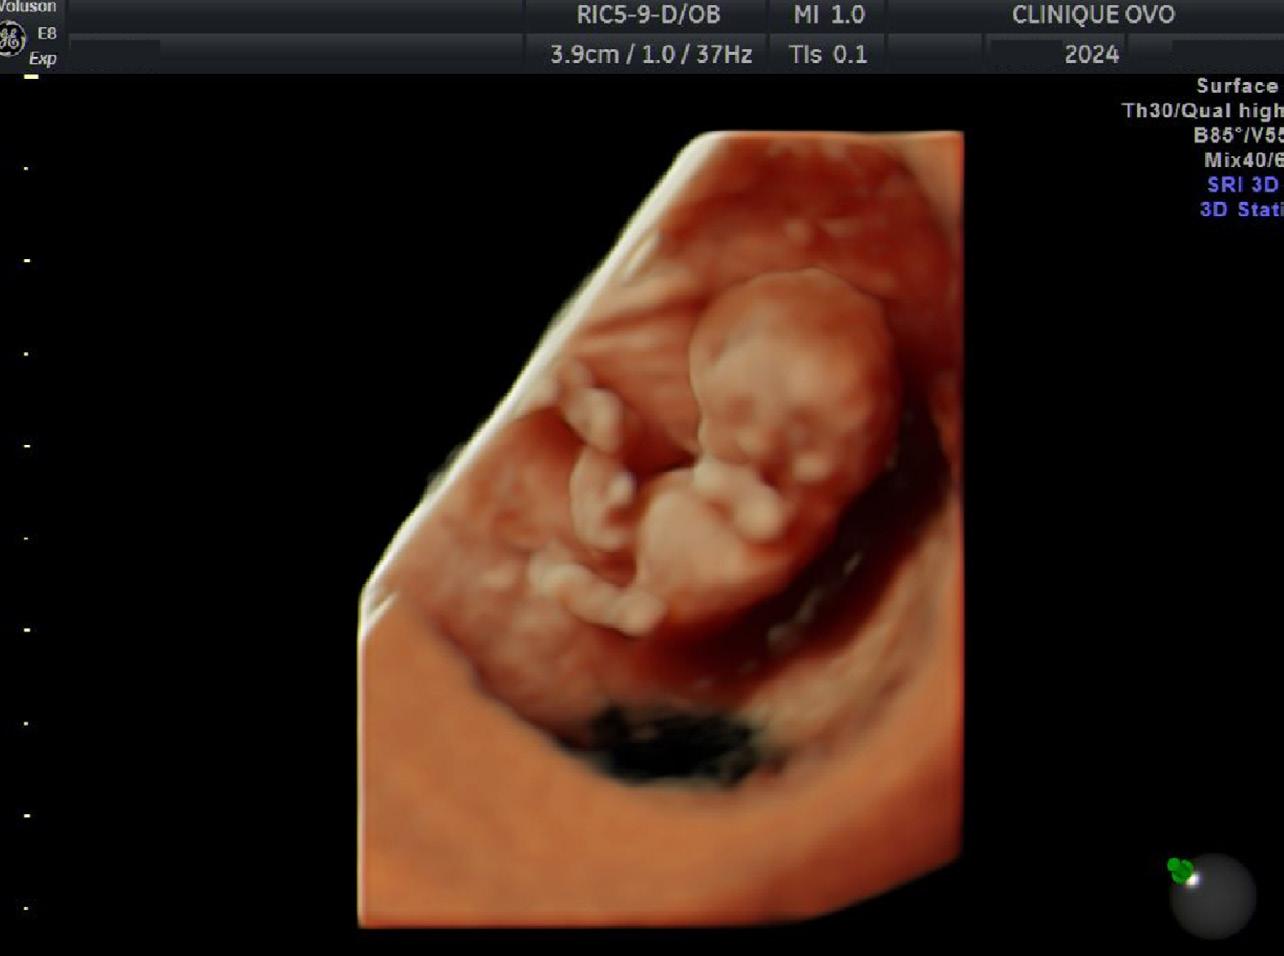

simplement ne pas y avoir de grossesse. Pendant l’échographie, on mesure la longueur de l’embryon, de la tête (rhombencéphale) à la pointe de la colonne ainsi que le sac vitellin (là où se nourrit l’embryon) (Figure 3). De plus, on fait un tracé de l’activité cardiaque en mode « M ». Selon les recommandations de la Fetal Medicine Foundation (FMF), on n’utilise pas le mode pulsé avant huit semaines de grossesse, parce l’embryon est encore en train de former ses organes2. On veut alors éviter d’accroître la chaleur des tissus à ce stade critique.

En échographie de viabilité, on peut faire une image 3D de l’embryon avec une teinte beige pour

imprimer une image plus réaliste que les patients peuvent conserver en souvenir (Figure 5). Cette simple image les aide à ce que la grossesse leur paraisse plus concrète.